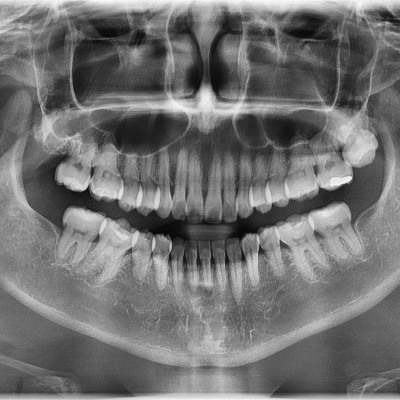

• 164

#48 사랑니 발치 N새글 #48 사랑니 발치 구강 외과 전문의가 당일 발치했습니다. -----------------------------..

작성자 이턱이 작성일 17:34 조회 1